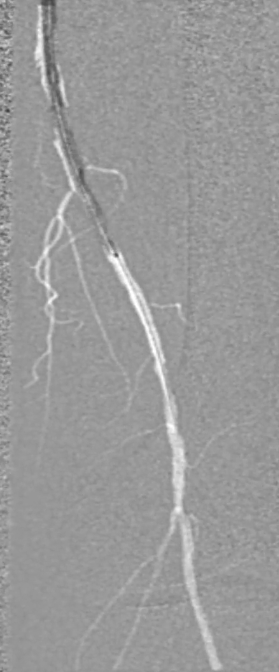

调整与确认:开通至股浅动脉中段后,发现导丝向另一个方向打弯,退回后重新选择路径,最终顺利送至股浅动脉远端真腔,造影证实开通成功。

考虑到超声导管的使用以及导丝通过时顺滑度,认为病变大部分是真腔通过,因此考虑对股浅动脉减容处理。

预扩张:先用3mm球囊对病变段预扩张,便于后续器械导入。

保护伞置入:于腘动脉P2段水平放入6mm Spider 保护伞,预防栓塞。

定向旋切:采用新一代Hawk-Plus定向斑块旋切装置进行减容。对于支架内闭塞段,放大图像,确保刀头在可视范围内,反复旋切至接近支架边缘;

对于支架远端病变段,分别采用4个方向各旋切1次,完成初期减容。